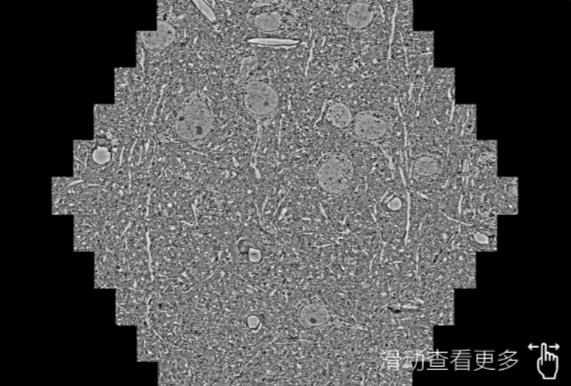

鼠脑切片。左图使用潜江蔡司潜江扫描电镜MultiSEM706对165μmx143pm面积区域成像,耗时仅需1.5秒。右图为鼠脑切片中30μm区域放大效果。样品由芝加哥大学B.Kasthuri提供。

使用蔡司高速潜江扫描电镜MultiSEM对1mm²人脑皮层组织进行高分辨成像,并对其中的各种细胞结构进行三维重构分析。左图展示了2x3mm²组织平面中锥体神经元的三维重构效果。右图显示了局部体积神经元三维重构。图像由哈佛大学chtman实验室提供,渲染图由D. Berger 制作。